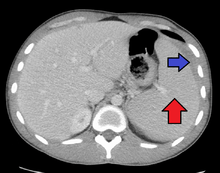

Spleen enlargement is common in the second and third weeks, although this may not be apparent on physical examination. Rarely the spleen may rupture. There may also be some enlargement of the liver.[20] Jaundice occurs only occasionally.[12][21]

Splenomegaly is a common symptom of infectious mononucleosis and health care providers may consider using abdominal ultrasonography to get insight into the enlargement of a person's spleen.[50] However, because spleen size varies greatly, ultrasonography is not a valid technique for assessing spleen enlargement and should not be used in typical circumstances or to make routine decisions about fitness for playing sports.[50]